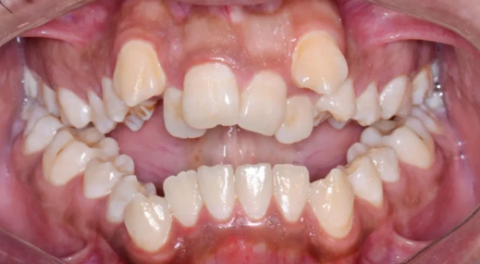

Based on the provided intraoral photograph, the primary and most significant diagnosis is Severe Maxillary and Mandibular Dental Crowding with associated Malocclusion.

Severe Crowding: There is a significant lack of space for the teeth to align.

Canine Impaction/Ectopic Eruption: The upper Canine (cuspid) teeth (the pointed teeth) appear to be severely displaced, erupting high above the arch (ectopic eruption). This is a common consequence of lack of space and may indicate an impacted status that required surgical exposure, or simply a severe malposition.

Midline Discrepancy: The upper front teeth (incisors) may not be perfectly aligned with the lower ones or the facial midline.

Arch Form: The arch appears constricted or "V-shaped" rather than the ideal broad, "U-shape."

Moderate to Severe Crowding: The lower anterior (front) teeth are visibly rotated and overlapping, indicating significant space deficiency.

Gingival Status: While not the primary focus, the crowding makes effective brushing and flossing difficult, which can lead to increased plaque retention, gingivitis, and potential periodontal issues in the future.

The severe crowding and canine position make a proper Class I (ideal) occlusion impossible. The case likely presents with an Angle's Class II Malocclusion or a complex variant due to the extent of the anterior displacement and crowding.

There appears to be an increased overbite (vertical overlap of front teeth) and potentially a deep bite, though a lateral view would be needed for a definitive assessment.